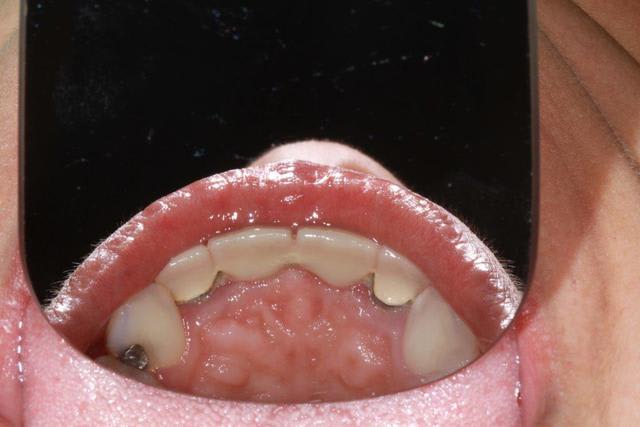

Patiente sympa, 30 ans, un bridge ceramo-métal fait il y a 10 ans, en fin de vie.

En réalité je sais déjà ce que je vais faire, mais implants, bridge ou pourquoi pas adjointe???